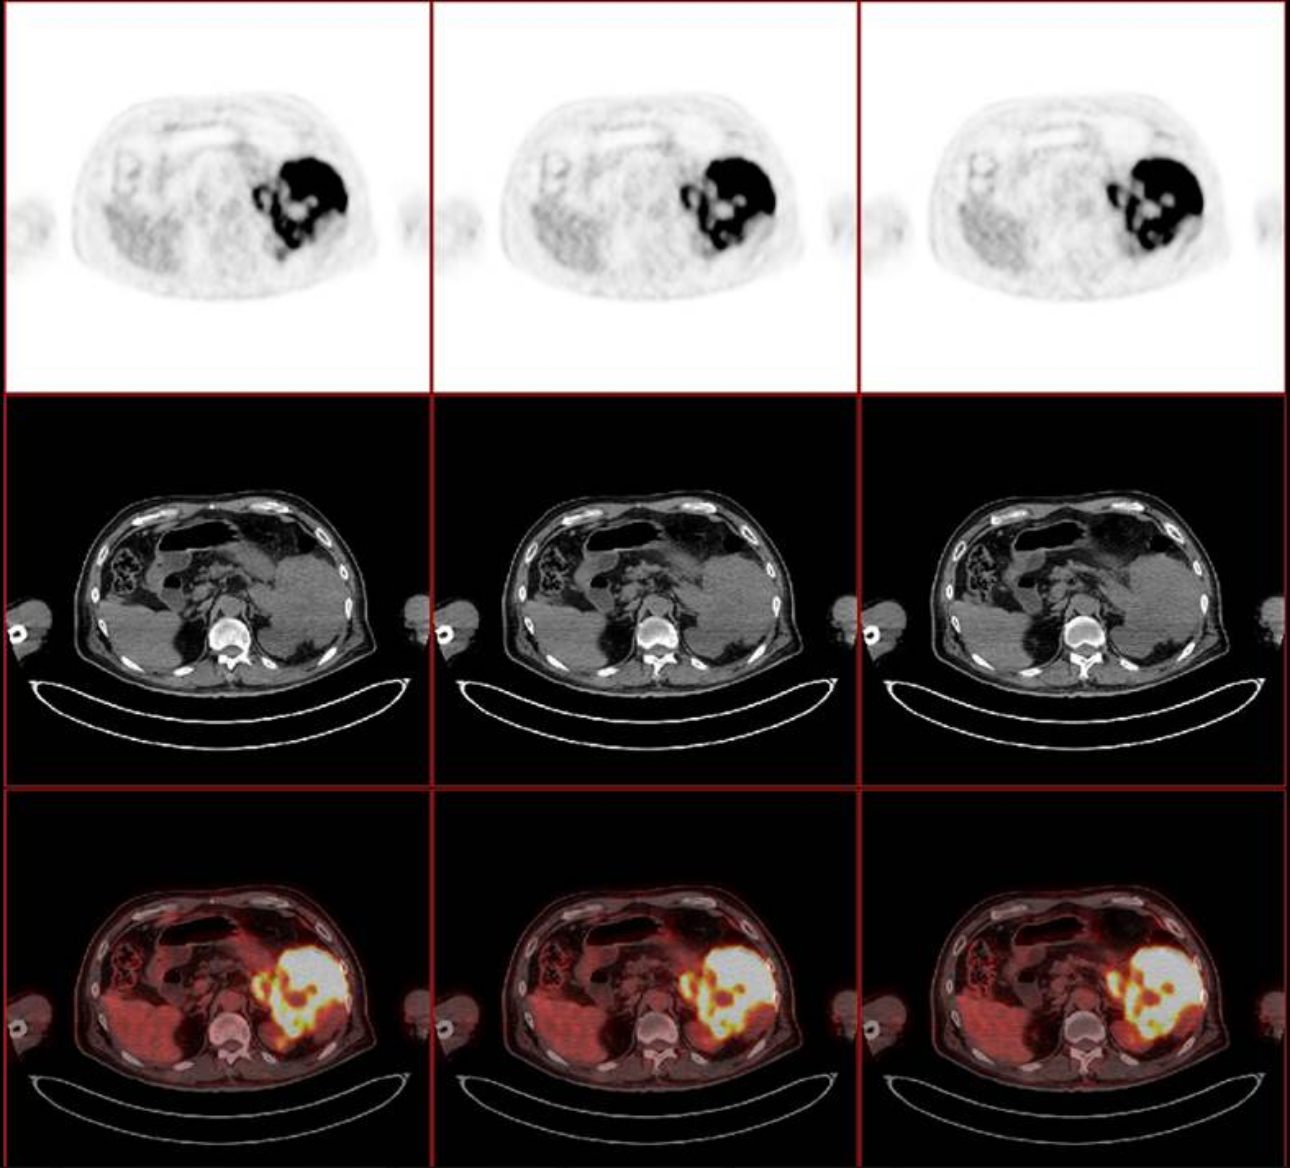

??? US, CEUS, CT ? ?? PET/CT ??? ???? ? ??? Fig 1-3? ????.

?? ?? ??? ??????? ????(nonspecific) ??? ???(primary pancreatic cancer)?? ????? ??? ?? ???(primary pancreatic lymphoma)? ?????(Burkitt lymphoma)? ???? ??? ?? ?? ??(pancreatic mass)? ?? ???????(ultrasound guided biopsy)? ???????.

??? ?????? R-Hyper-CVAD-A ????? ???? ??? CT ??? ?? ?? ??? ??? ??? ?? ?? ? ? ????. (Fig 4 A-C). ??? ???? ??? ?? ??? ??????.